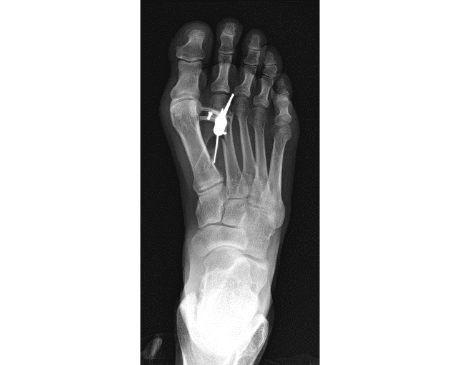

I was hit by car, had a compound fracture with a bone sticking out of my left foot. Broken tibia and fibia?. Screwed plate and bones back together. I am healing fine, next visit 3/26 to remove stiches. I seem to have total function of foot. Still have 2 more weeks of not using leg, but very hopeful.